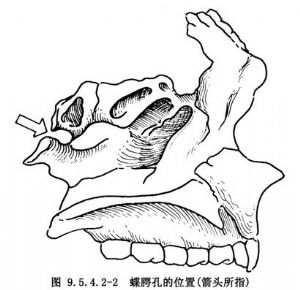

鼻咽部血管纖維瘤主要發生於青春期前及青春期男性。屬組織學良性而具有生物破壞性(biologically aggresive)腫瘤,常沿自然裂隙或孔向周圍擴展並破壞周圍組織,向前可侵及鼻腔、後組篩竇、蝶竇、眼眶,直至海綿竇及蝶鞍周圍,向外可通過蝶齶孔侵入翼齶窩;又通過翼頜裂侵入顳下窩。腫瘤以蝶齶孔處爲根形成向兩端膨大的啞鈴形(圖9.5.4.2-1,9.5.4.2-2),還可經眶下裂跨過眶尖進入眶上裂,侵蝕翼板基部及蝶骨大翼而抵達顱中凹處的硬腦膜(圖9.5.4.2-3)。

過去認爲,腫瘤的原始發生部位可能是鼻咽頂部或鼻後孔處。近年來有人認爲蝶齶孔處可能是腫瘤原始發生部位之一。因爲有些腫瘤儘管以蝶齶孔處爲莖呈啞鈴狀,但蝶齶孔並未擴大,也無侵蝕現象。只有腫瘤原始發生於蝶齶孔,並同時向鼻咽腔及翼齶窩擴展,才能解釋這一現象。因此,在考慮手術途徑時,必須考慮到充分顯露蝶齶孔,纔不致殘留腫瘤組織。